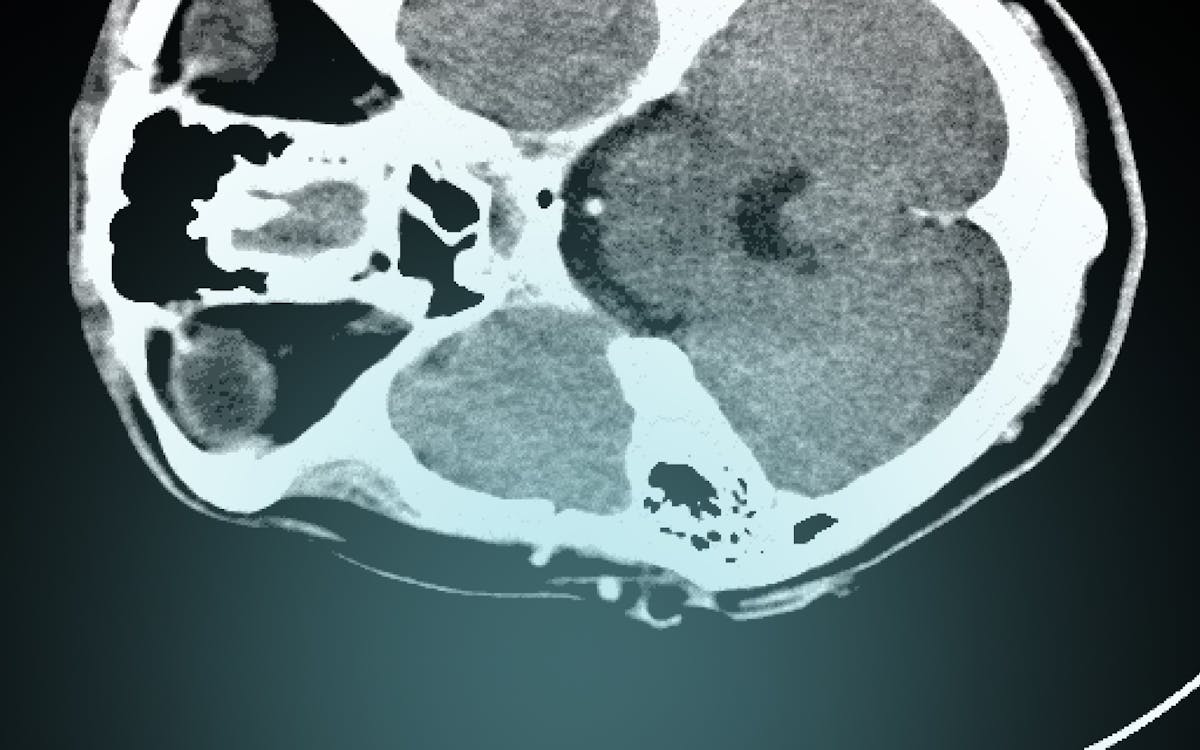

Marc Trabsky was recently interviewed by Karin Derkley for the Law Institute Journal on forensic imaging technology in Victoria. Karin writes that "Victoria leads the world in the use of forensic scanning technology to determine cause of death, but the legal profession is yet to fully embrace its benefits". Marc is quoted as saying "forensic scanning creates a more objective and accurate investigation of the medical cause of death. 'It also creates a more permanent record and a way of discovering the cause of death without doing damage to the body.'"